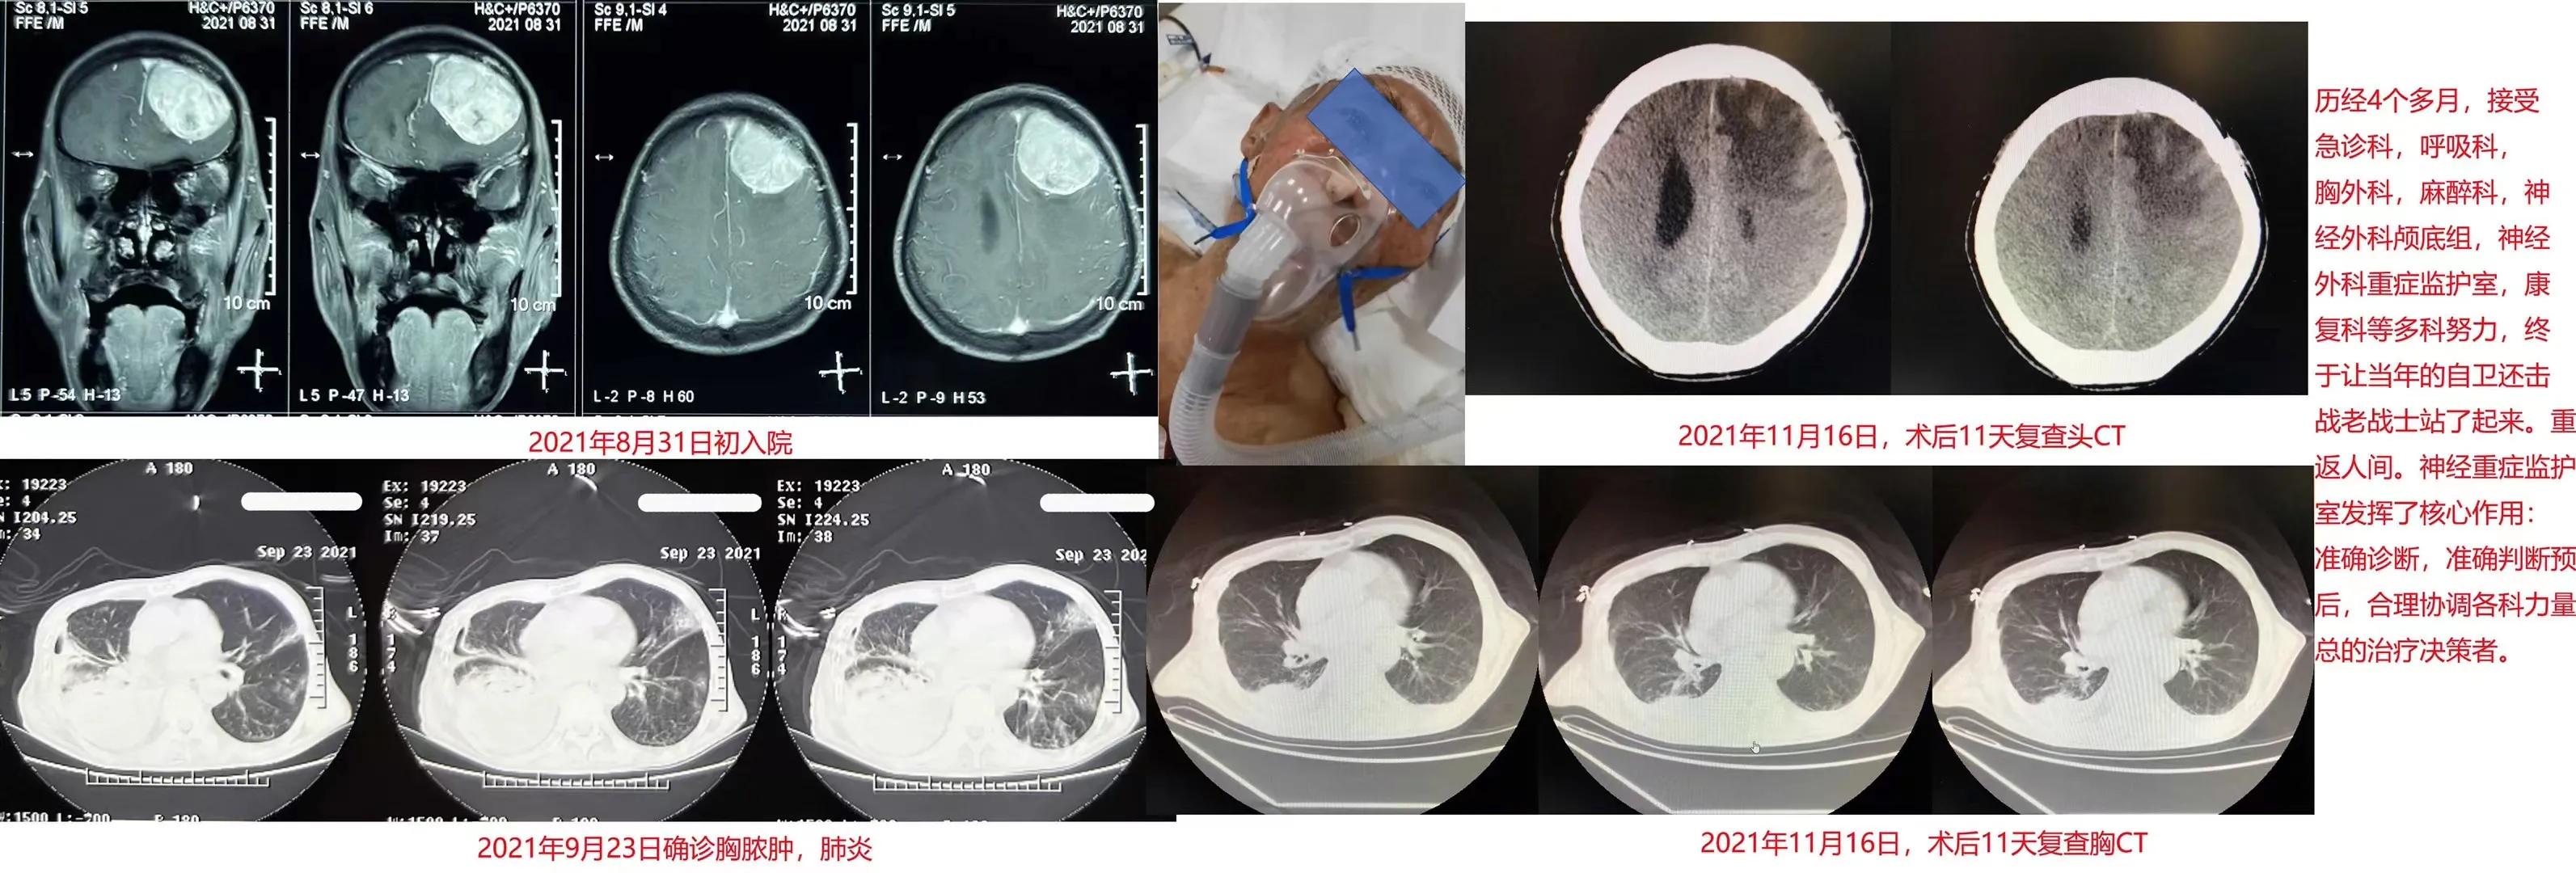

我被通知去会诊时,他已经在我们急诊科的观察室躺了十几天。我第一眼看到他时,他蜷缩成一团躺在病床上。他身高超过175cm,但非常瘦弱,估算体重也就80斤左右。此时正闭着眼,慢性病容,气喘连连。我试着叫他,观察他的反应,发现刺痛他只是可以睁眼,但不能言语,肢体可动,而右侧肢体明显更差,右手还微微颤抖。我查看他的化验和检查,发现他左额长了一个巨大肿瘤,按其形态特点可以诊断为脑膜瘤,脑子受压严重。而他的化验结果竟满目都是异常值,包括重度贫血、炎性指标飙升。问家属他的饮食情况,才知道患者4年前已经诊断脑膜瘤,但因为症状轻微,只服偏方治疗。近一个月不能进食,吞咽障碍,卧床不起……其他医生对这个患者的治疗没有信心,患者就一直留在急诊……我觉得在神经外科已经进入显微镜和内镜时代的今天,手术全切这样的肿瘤应该不成问题,这样的患者应该绝大多数可以治愈,而不应该死亡或重残。短时间内,我做了判断:患者右额脑膜瘤,有手术指征。但是,目前极度营养不良,恶液质,可能还有其他潜在疾病,一息尚存,非常危重,又具有明确的手术禁忌。引起手术禁忌症的主要原因是脑膜瘤巨大、压迫脑组织,导致了多器官损伤,引起全身状况迅速急转直下,生命垂危。脑肿瘤是导致上述所有危重临床症状和体征的根源。如果不去掉肿瘤,必死无疑;而现在贸然去切肿瘤,相关并发症则可能让患者更早死亡。此时应该发挥NICU内有良好的监测和各种改善呼吸与循环设备设施的优势,将患者转入NICU,力争通过支持疗法,为患者赢来一个切除肿瘤的宝贵时机,进而挽救他的生命。

我把他收进了NICU。他的情况比预想的还要差:嗜睡失语,血压低到休克,重度贫血,右侧脓胸,右胸塌陷,营养不良,可疑帕金森……不能进食,没有胃管……我的下级医生怀疑这样的患者即使积极救治也没有生存希望。我反对这样的判断,认为造成患者今天这个局面的关键因素是脑肿瘤增长导致慢性脑疝引起的多器官受损,而这是良性可切除肿瘤,只要纠正手术禁忌证,全切肿瘤,就可能为患者赢得生机,而NICU良好的设备设施和生命支持经验,可以为患者提供短时间支持。再协调各方力量,应该可为患者创造手术机会。在我的激励下,我的团队积极救治患者。一边积极营养治疗,一边求助于胸外科、呼吸科、感染科和神经内科,获得专家们的帮助:脓胸穿刺外引流,间断补血,补充肠内营养,调整抗菌素……经过长达40多天的NICU治疗,患者的胸脓肿引流明显减少。虽然脓胸治疗周期经常需要长达半年,还远不到拔除引流管的时候,患者也仍间断有低烧,但患者生命体征和化验基本稳定,已经基本扫除了手术禁忌证。而且,此时如果不做手术,可能就永远做不了手术,因为对于这样一位从恶液质状态救治过来的患者,他能接受大手术的机会稍纵即逝……科主任岳树源教授帮我主持了多科大会诊:麻醉科主任自信可以保障好气管插管全麻手术,胸科主任认为脓胸导管不影响手术,呼吸科主任认为肺功能可以耐受一次手术打击,而作为当下中国医师协会脑肿瘤专业委员会主任委员的岳树源教授则自信可以用最短的时间结束手术,使患者脑损伤最小……家属虽然不懂医,却依从性良好,果断接受一次冒着巨大风险的手术。2021年11月5日,手术如期开展。尽管肿瘤血供丰富,质地坚硬,岳树源主任仅用不到2小时就完成了肿瘤的切除,失血量仅100ml左右,为患者赢得了生存转机。

术后患者仍极度消瘦,也仍不能起床和言语。但明显双眼有神,肢体活动好转。我们又适时请康复科专家介入,在康复科住院约15天,症状体征均得到进一步改善。患者终于出院了,出院时尽管仍然是卧床状态,但经口已经可以少量进食。我的团队也坚持随访,给家属康复建议,鼓励患者从床头逐步抬高到慢慢坐起来,下地……2022年1月25日,患者出院回家已经2个多月,我们对患者进行了最新的电话随访,得知患者已经拔除了脓胸引流导管,能独立看电视和经口饮食,能拄拐站立,能靠助步器支持行走几步……我们的努力没有白费,又挽救了一条生命。